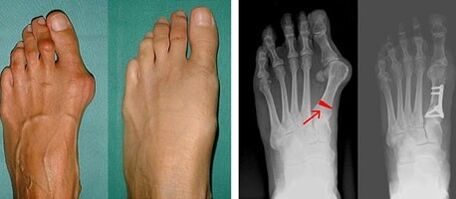

If visual examination and X-ray do not give a result, the patient is referred for plantography to detect possible flat feet.With this method, impressions of the feet are made, on the basis of which shoes or insoles with orthopedic properties are made for the patient.The patient is then prescribed podometry.This method uses computer analysis to determine the pressure of a person's weight on their feet.The results of advanced diagnostics are the basis for choosing a method of treatment for curvature of the first and second toes.

At the first stage of detecting valgus of the big and little toes, the doctor conducts a visual examination.In this way, the level of development of the pathology is determined.To detect detailed joint changes, x-rays and plantography are prescribed.